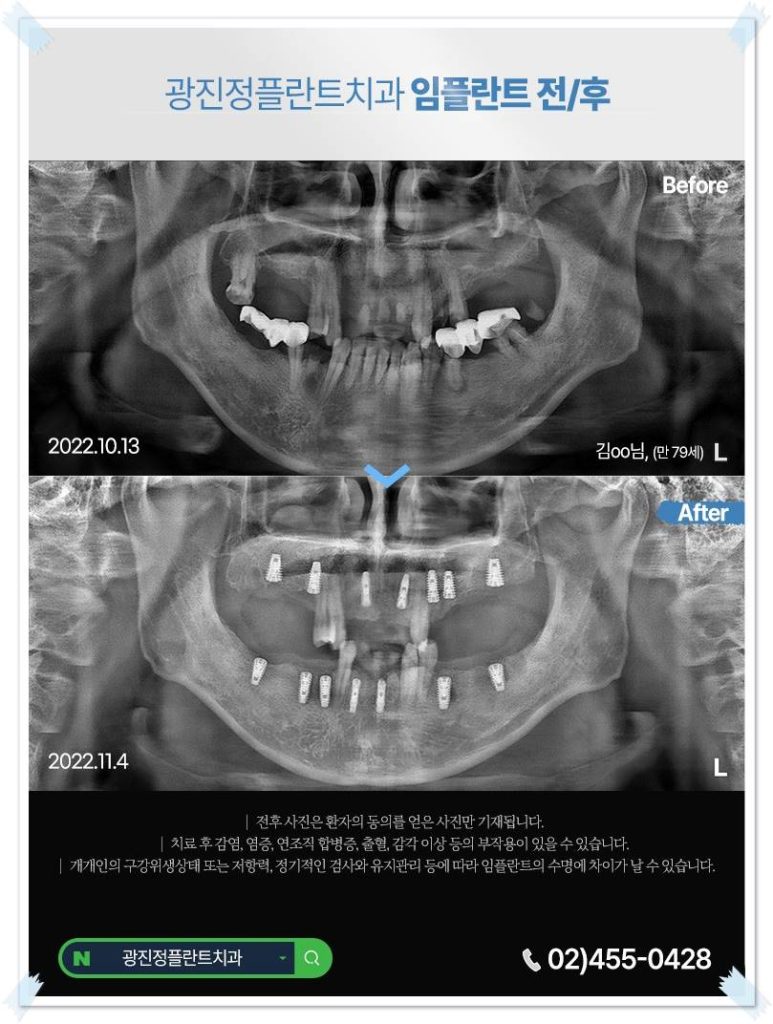

광진구(자양동, 구의동, 광장동 등)에서 오랫동안 한 자리를 지켜온 치과를 찾으세요. 임플란트는 식립보다 ‘사후 관리’가 수명을 결정하기 때문입니다. 정기 검진 시스템이 잘 갖춰진 곳인지 꼭 확인하시기 바랍니다.

본 포스팅이 광진구에서 어금니 임플란트를 고민하시는 분들께 실질적인 도움이 되었기를 바랍니다. 광진정플란트치과에서 작성한 글이며 더 궁금하신 점은 02-455-0428 통해 문의해 주세요.